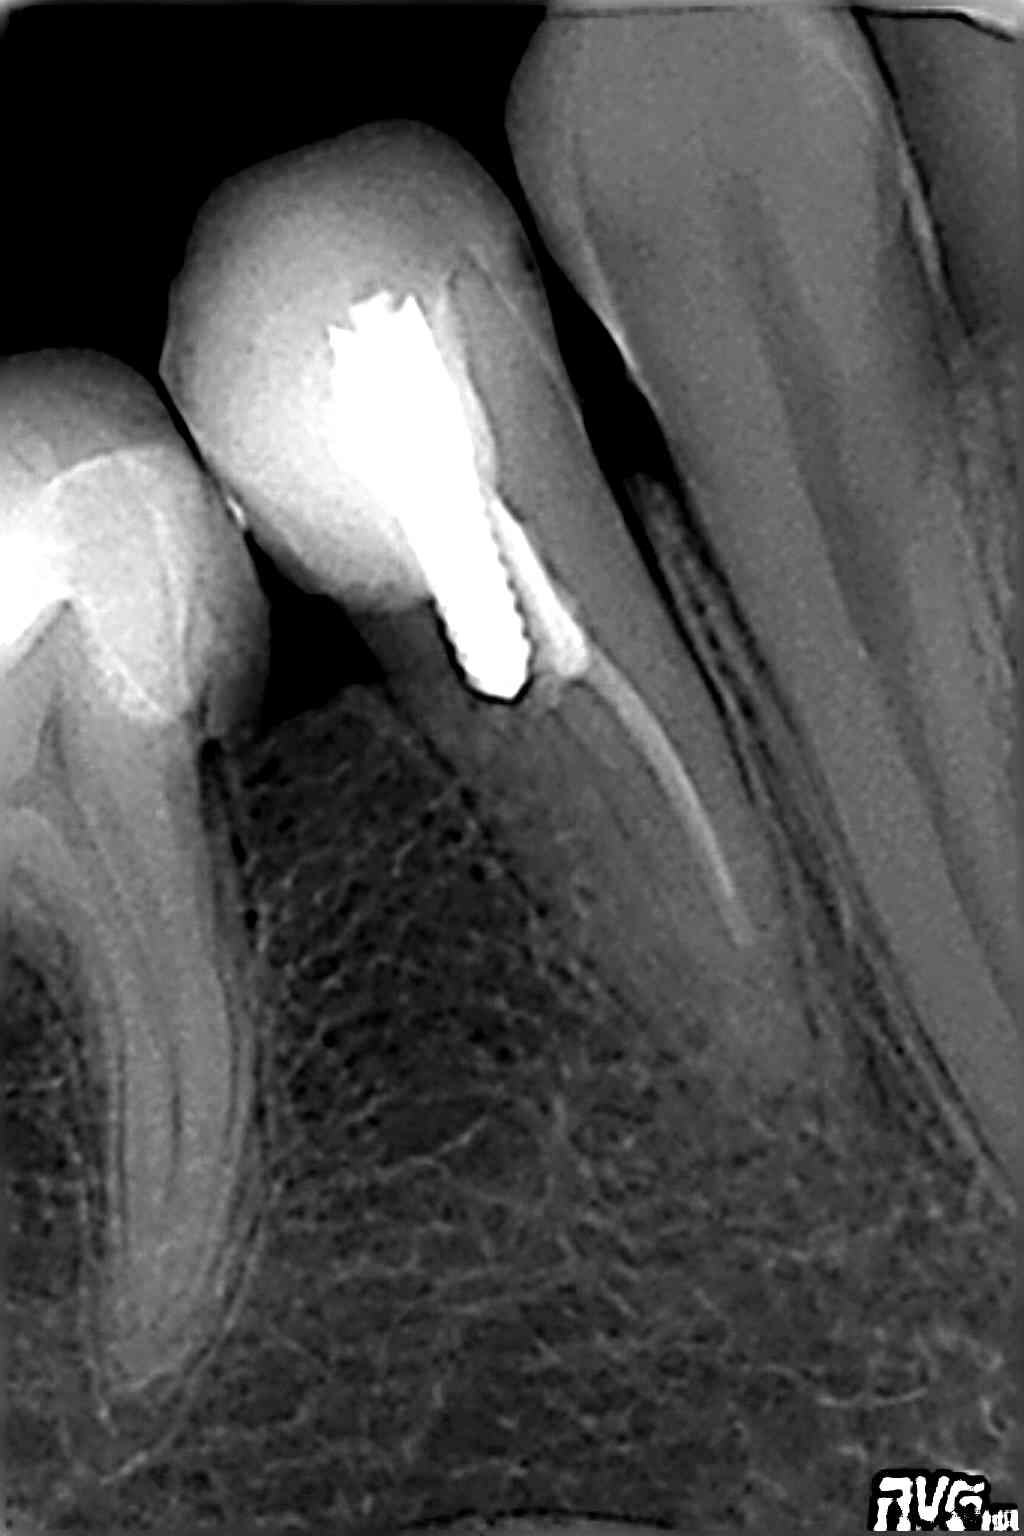

Radiowizjografia jest podstawowym narzędziem do diagnostyki, oraz kontrolowania przeprowadzonego zabiegu stomatologicznego.

Takie dziedziny stomatologii jak implantologia czy endodoncja nie mogłyby być skutecznie wykonywane bez cyfrowych systemów radiologicznych.

W odroznieniu od standardowego RTG, radiowizjografia eliminuje tradycyjną kliszę rentgenowską, która zostaje zastąpiona specjalnym czujnikiem, dzieki któremu od razu uzyskujemy wysokiej jakości obraz na ekranie komputera. Technika cyfrowa dzięki możliwości zastosowania kontrastu, powiększenia wybranego fragmentu obrazu, dokonywania pomiarów pozwala na nieporównywalnie dokładniejszą ocenę sytuacji klinicznej niż tradycyjne zdjęcie RTG.

Radiowizjografia pozwala obniżyć dziesięciokrotnie dawkę promieniowania w stomatologicznych zdjęciach wewnątrzustnych w porownaniu z standardowymi zdjęciami wykonanymi na kliszy.

Dzięki łatwości archiwizacji i dostępu do danych mamy możliwość analizowania efektów leczenia i kontroli stanu uzębienia na przestrzeni wielu lat.